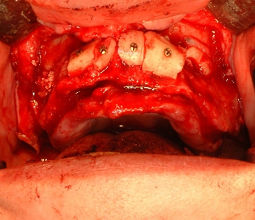

19歳女性:左側上顎犬歯部に自家骨移植により骨を回復した写真